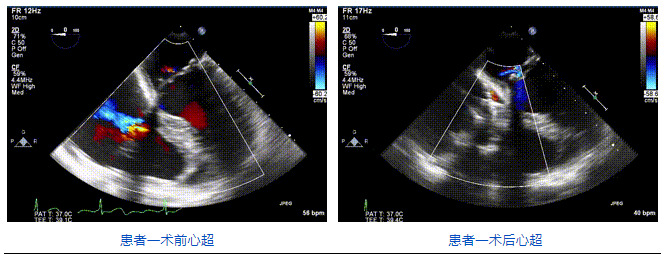

三例患者入院后,葛均波院士團(tuán)隊周達(dá)新教授、潘文志教授、張源博士、陳莎莎博士及心超室的潘翠珍教授、李偉教授對患者的情況進(jìn)行詳細(xì)評估和討論,最終決定為三例患者選擇LuX-Valve Plus40mm、50mm和50mm型號的瓣膜進(jìn)行手術(shù)治療。手術(shù)后即刻拔除氣管插管,術(shù)后患者三尖瓣反流癥狀得到顯著改善,復(fù)查心超結(jié)果顯示人工三尖瓣瓣膜支架固定穩(wěn)定,瓣葉關(guān)閉形態(tài)未見異常,未見明顯反流。